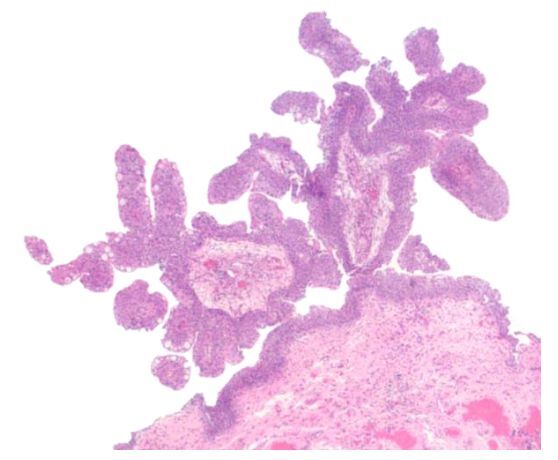

Nope, just an inverted urothelial papilloma.

Note how benign and bland the individual cells look. Typically 5-10 cells thick with a smooth stroma-epithelial interface and no stromal reaction.

There may also be some cystic lesions, like cystitis cystica associated with Von Brunn nests.